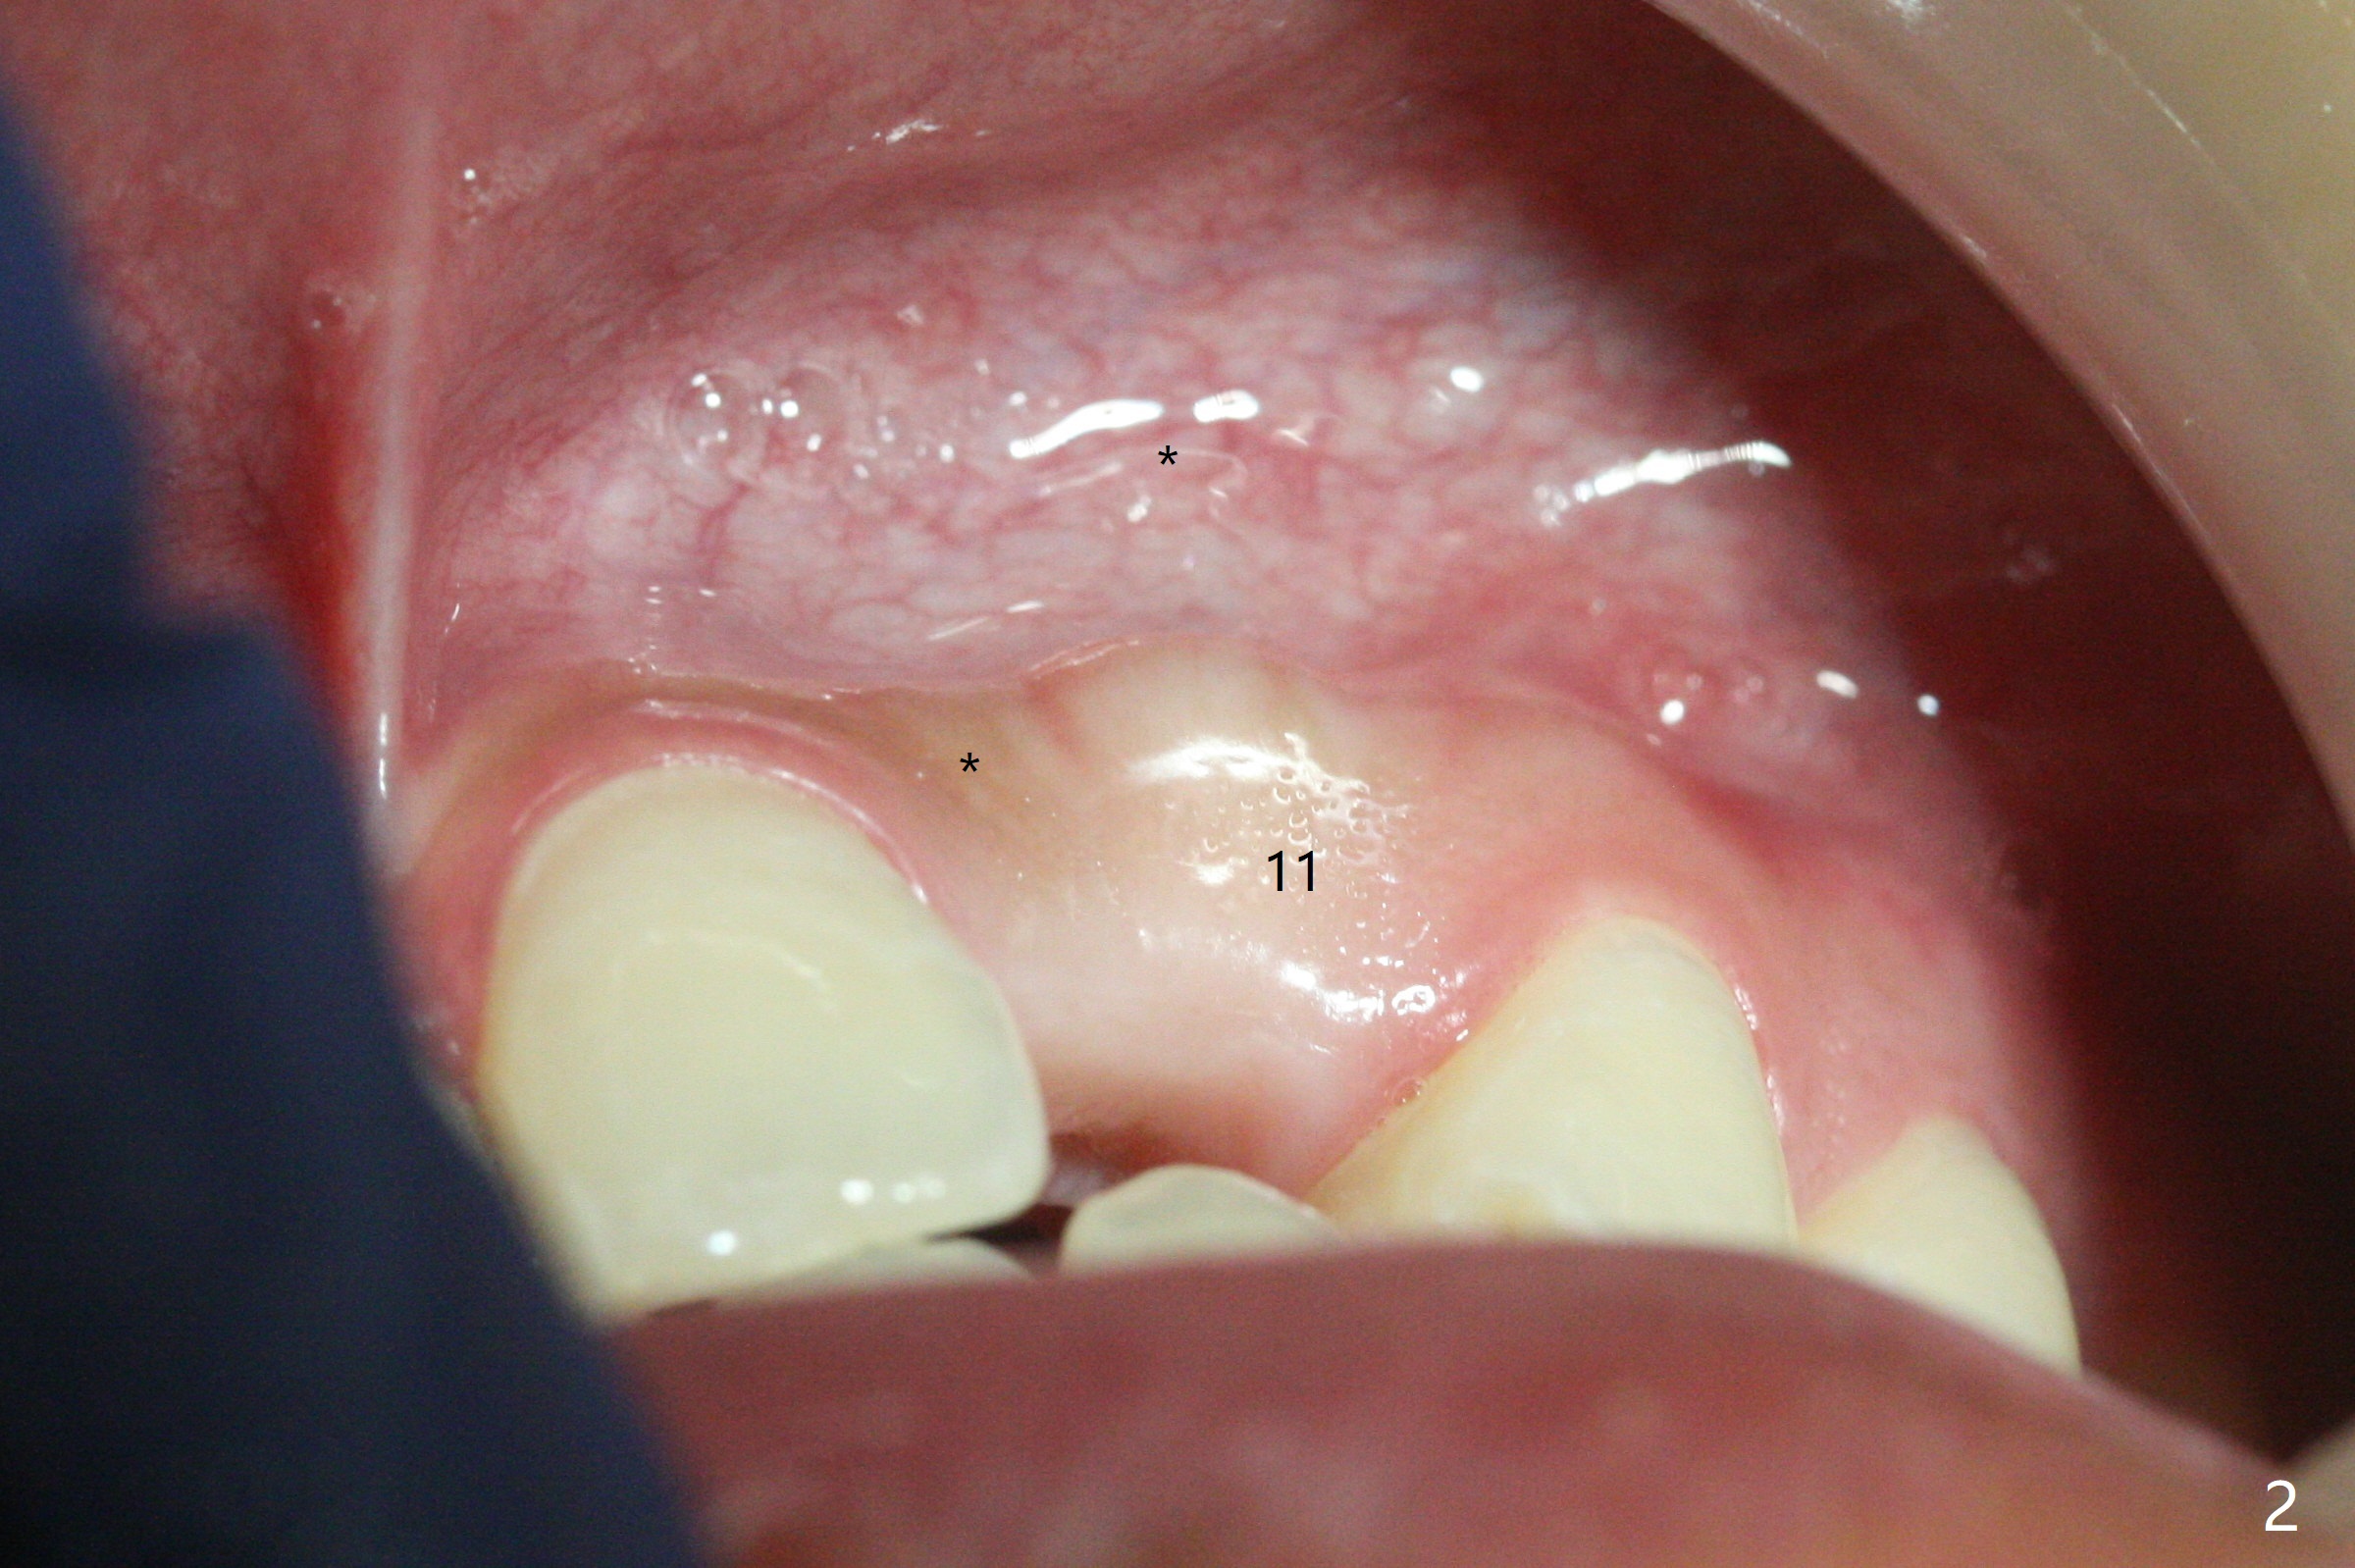

18岁男,本月底到外州上大学,急于十九岁前完成治疗,保险可以多付些。术前检查显示双侧尖牙(图一,二 6,11)根尖,侧切牙牙槽嵴萎缩(*),尖牙、侧切牙之间颊侧做垂直切口,骨膜下潜行分离,在尖牙根尖隧道植骨,然后使用导板,植入窄植体(图四至六),接近或者穿过上颌窦底板(图三,四箭头),骨粉(粘性骨块做的不成功,图五,六 *)好像覆盖暴露的螺纹。再次补充隧道骨粉后,放置修复基台(图七,八),调整后(图九),取模做临时悬臂桥,临床上有些困难分配尖牙,侧切牙比例。术后4个月左侧植体愈合正常(图十,十一),而右侧感染。